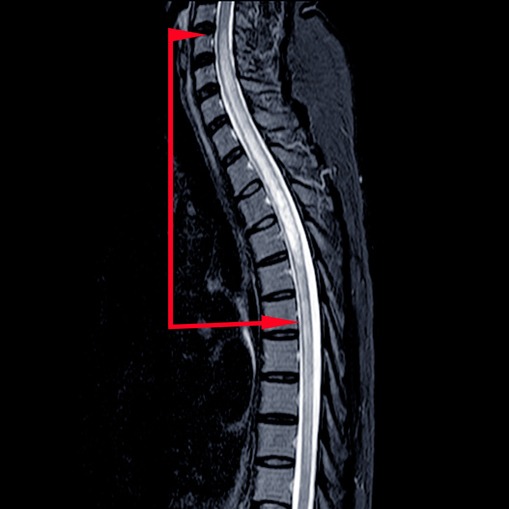

• imaging mediante risonanza magnetica: utile per individuare lesioni strutturali della colonna vertebrale che possono aver danneggiato il midollo spinale;